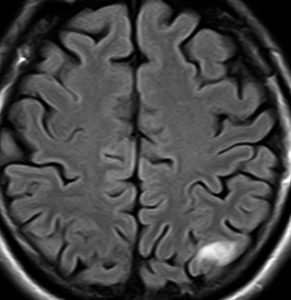

2000年頃の例です。てんかんで発症した20代の女性です。左前頭葉のグリオーマで,手術でほとんどで摘出 subtotal removalして,深部白質に残った病変を経過観察しました。MRIは術後のものです。Ip, 19qはFISHで欠失なし。MIB1は1-2%と低く,MGMTメチレーションなし,diffuse astrocytoma WHO grade 2と組織診断されました。大学病院でしたが当時はIDH遺伝子診断はしておらず,びまん性星細腫グレード2でした。これもまた当時の標準的な考えで,進行があるまでは経過観察としました。

2年後に急激な進行 rapid progressionしました。ガドリニウム増強所見も出現しました。IMRTで59.4Gy/27分割の放射線治療とテモゾロマイド化学療法をしましたが,腫瘍は抑制できませんでした。

放射線治療後も進行して,白質に沿った浸潤伸展をしました。脳幹部橋の右側まで浸潤 invasionしています。この伸展は星細胞系腫瘍の特徴でもあります。

2016年分類では,diffuse astrocytoma WHO grade 2です。しかしこれはおそらく,2021年分類では IDH wild-type astrocytoma grade 4とされます。